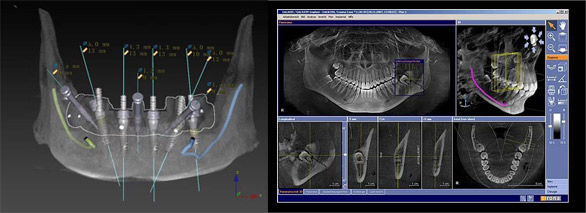

CBCT锥形束CT

360度旋转扫描即得患者骨量信息、软组织信息、咬合关系等头部完整数据,重组三维立体图像,超高清低辐射,医生可从任意角度观察分析病例。

数字化种植牙方案设计

整合患者口内的CBCT数据及咬合关系,将完整数据上传到会诊系统中,与数据库内数万病例进行综合对比、分析,规避术中并发症,模拟手术过程及预测术后治疗效果,以数字化全息影像为基础的方案设计对于患者来说更形象、更易懂,患者参与度更强。

导板引导种植手术

3D种植导板能实现手术虚拟设计的临床转化,准确地按照术前规划的手术方案进行手术操作,避免手术过程中各环节可能产生的误差,缩短手术时间,减少手术创伤,降低术后肿胀、疼痛、感染等并发症的发生风险。